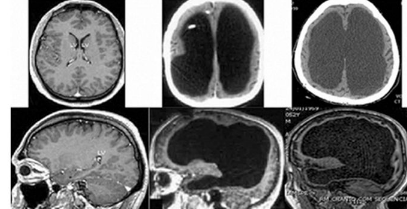

それはイギリスでの出来事。とある小児科の医師のもとに1人の学生が訪れました。頭に痛みを覚え、腫れている感覚があると訴えたのです。医師は症状の原因を把握するべく、脳のMRIを撮影したところ、目を疑ったのです。なんと、学生の頭蓋骨には脳がありませんでした。本来、脳がある部分には脳脊髄液で満たされており、深刻な脳水腫であることが判明したのです。

一般的な脳の重さは約1.5kgほどですが、その学生の頭蓋骨の中は約300gの脳脊髄液とこれを保護する膜のみでした。さらに衝撃的だったのは、学生は脳が無くとも日常生活に全く支障をきたしておらず、IQ126という、普段から非常に優秀な学生だったといいます。

医師はこの信じられない事実を確認するべく、研究を始めます。その学生と似ている脳水腫患者600人の脳を精密検査しました。その結果、全体の患者のうち、60人が脳の95%が無い状態でした。

中には、医師を「MRIの写真の解析を間違えている」と研究を否定した学者もいましたが、圧倒的に支持する学者の方が多いのが事実です。現在もこの研究は行われており、最近も学術誌にこの事実が掲載され、話題になったようです。正直言うと、脳は心臓よりも重要な役割を果たす部分ですが、脳は無くともIQには影響がなく、普通に生活できるという事実は驚きを隠せませんね。